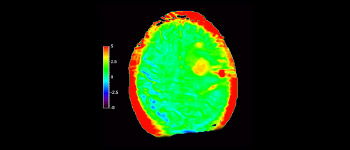

Maggiore affidabilità diagnostica in neuro-oncologia